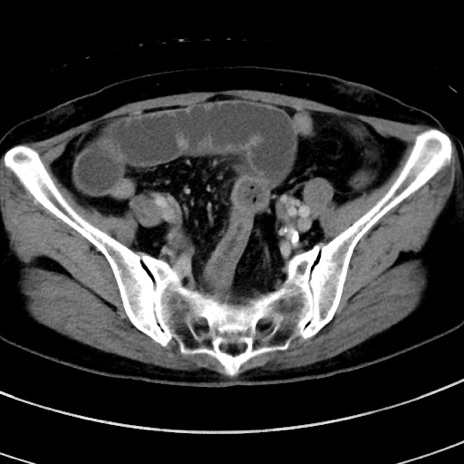

症例9(横断像)

【症例】 60歳代女性

【主訴】むかつき、みぞおちの痛み

【現病歴】3日前よりむかつきがあり、食事がとれない。

【既往歴】糖尿病

【身体所見】発熱なし、心窩部圧痛軽度あるも、腹膜刺激症状なし。

【データ】WBC 7400、CRP 1.92